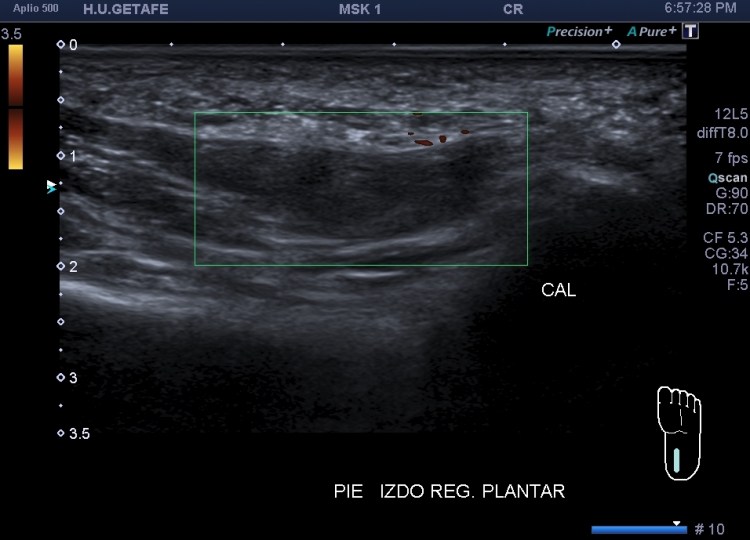

En este caso final una mujer acude a realizarse una ecografía con una petición de su médico de cabecera, viene por aumento del calibre del muslo anterior, no refiere dolor, no cuenta traumatismo previo.

La exploración es la habitual, revisión sistemática de toda la ecoarquitectura musculoesquelética de la cara anterior del muslo, dirigido al Cuádriceps.

Me llama poderosamente la atención, lo recuerdo perfectamente, la normalidad del recto anterior, pero después de buscar un poco observo como el vasto intermedio si está «distinto», algo heterogéneo, voy a comparar con el lado contralateral y bingo¡ el vasto intermedio, que es de esa musculatura «que nunca tiene nada», modo «ironía on», te sorprende…y la ecografía muscular es como el océano, nunca puedes confiarte…

Mira las imágenes y tu misma te darás cuenta:

La zona que presenta mayor abombamiento y empastamiento (cara lateral del muslo izquierdo), se visualiza aumento del grosor del fascículo muscular correspondiente con el vasto intermedio, sin poder evidenciarse la presencia de lesiones definidas. El diagnóstico es un aumento difuso e inespecífico del Vasto Intermedio, sin masas ni roturas. A valorar con RMN.